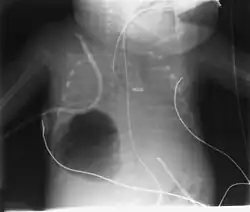

Die Diagnose ergibt sich aus dem Röntgenbild, auf welchem eine scharf begrenzte umschriebene luftäquivalente Aufhellung sichtbar wird. Bei der Lunge genügt eine Übersichtsaufnahme, während an der Schädelbasis eine Computertomographie notwendig ist.